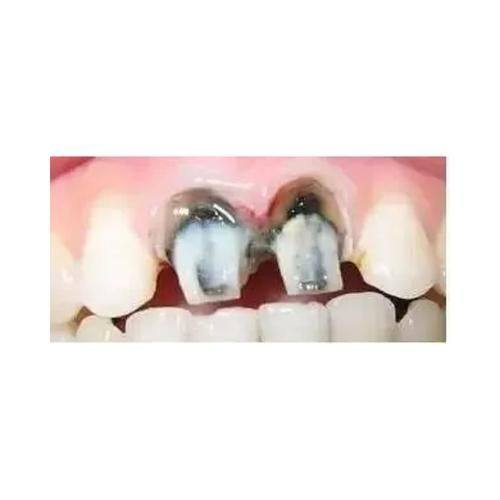

4. 根管治疗:500 - 1500元

3. 我经常牙疼,到同泽口腔检查后发现是牙髓炎,需要做根管治疗。医生特别耐心地给我讲解治疗过程,消除了我的顾虑。治疗后,牙疼的问题完全解决了,而且治疗费用也特别合理,以后看牙就认准同泽口腔了。